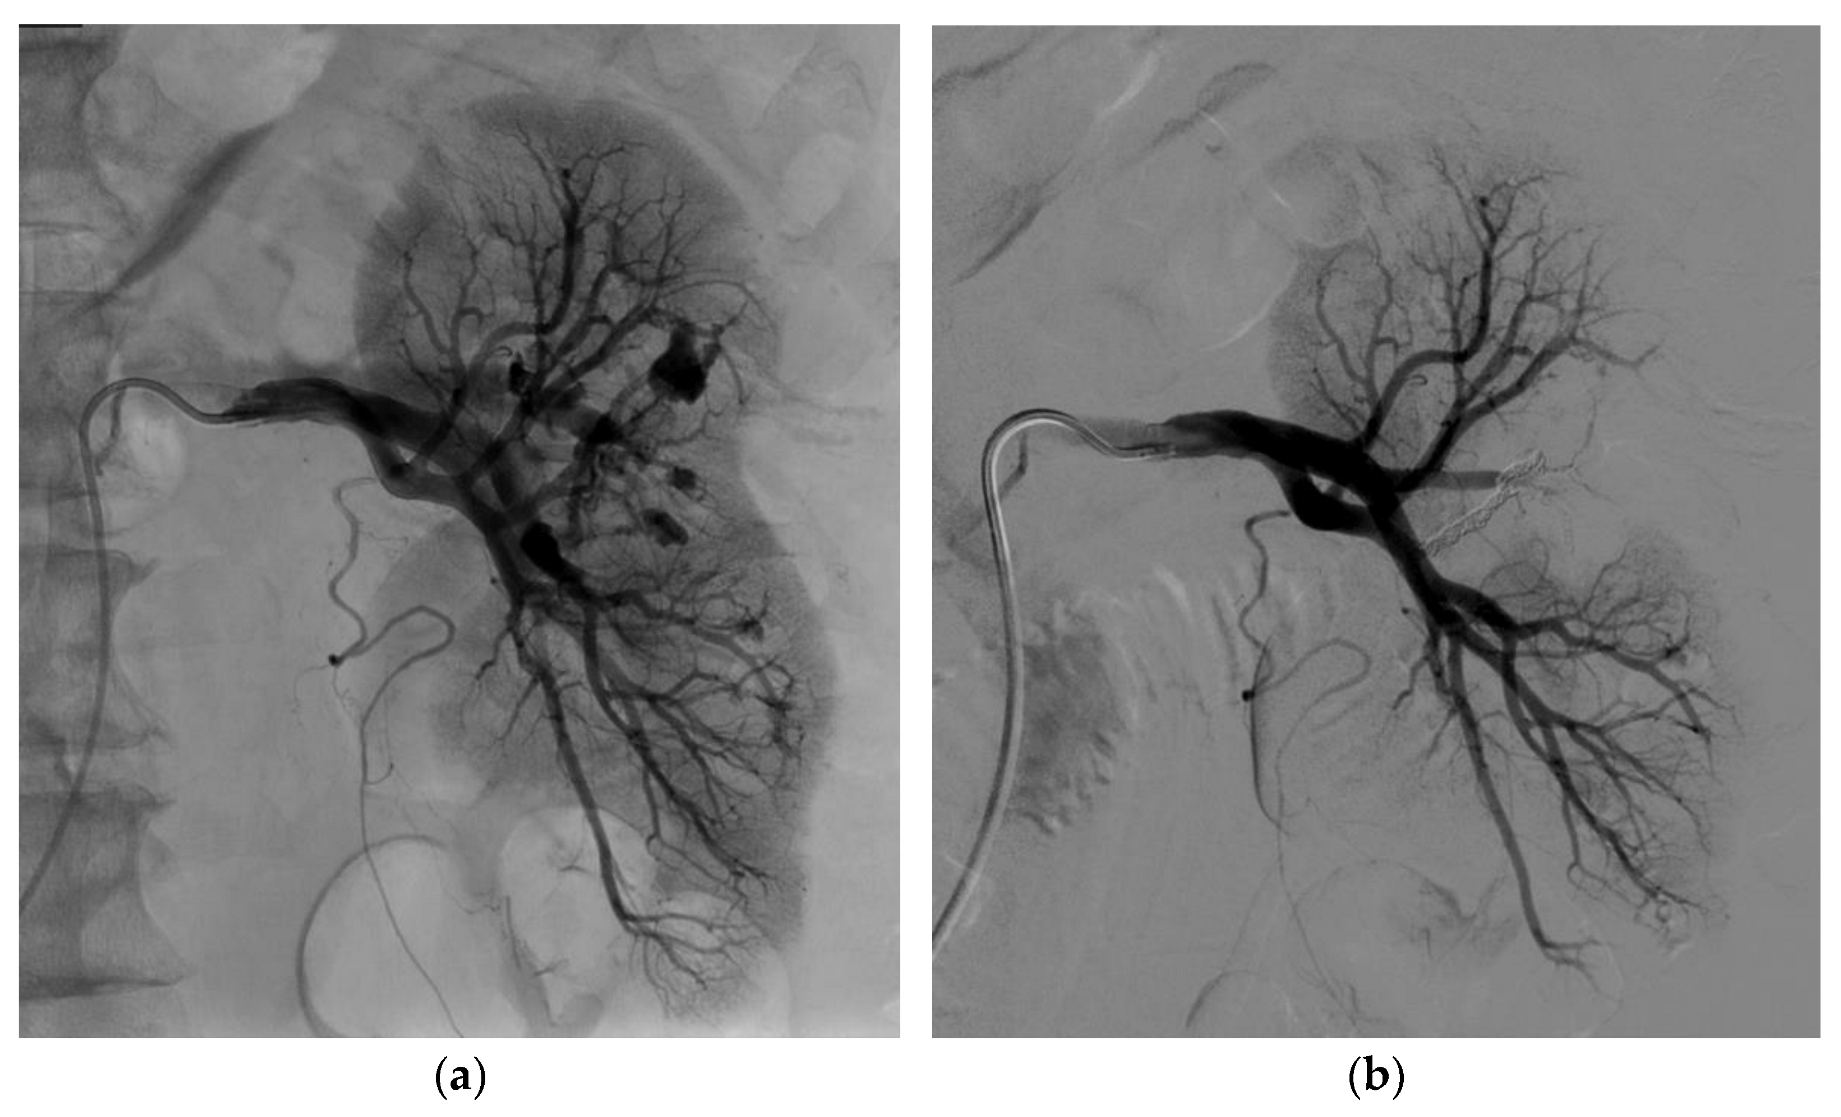

3.2. Endovascular Treatment

| Embolization technique | |

| Coils | 8 (32%) |

| Liquid embolic agent | 8 (6 Glubran2, 1 Onyx, 1 Gelatispon) (32%) |

| Coils and liquid embolic agent | 9 (36%) |

| Technical success at first attempt | 24 (96%) |

| Technical success at first or second attempt | 25 (100%) |

| Clinical success, one attempt | 24 (96%) |

| Clinical success, one or two attempts | 25 (100%) |

| Fluoroscopy time (min and s) | 25 min 12 s (±19 min 35 s) |

| Radiation dose (mGy·cm2) | 177,046 (±115,481) |